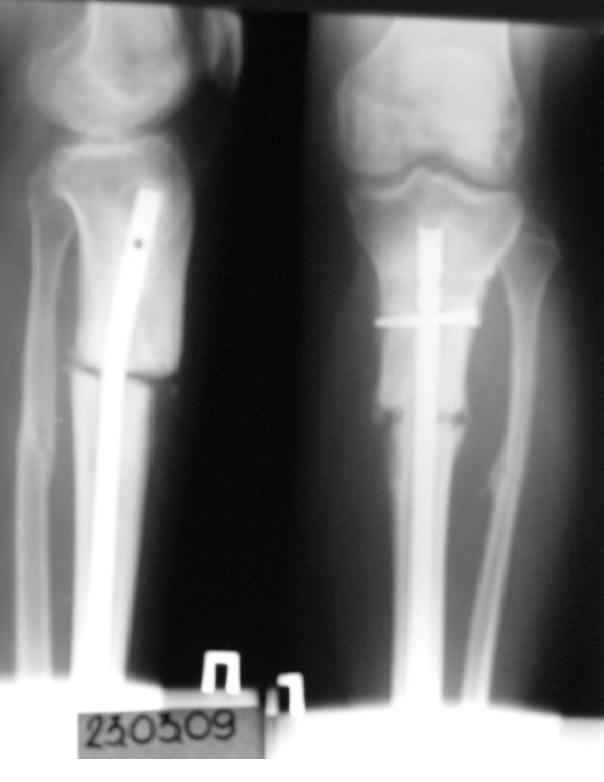

Имя     : 7.06.08.JPG

Тип     : image/jpeg

Размер  : 11286 байтов

Url     : http://weborto.net:8080/pipermail/ortho/attachments/20090417/b6bc8f23/attachment-0004.jpeg

История следующая: женщина (медработник)сбита машиной 7.06.08 - о.перелом обоих костей

голени в/3 со смещением. В ПДО ПХО раны,вытяжение за пяточную кость. После заживления раны

20.06.08 выполнен остеосинтез блокирующем стержнем. в течение первого месяца после травмы